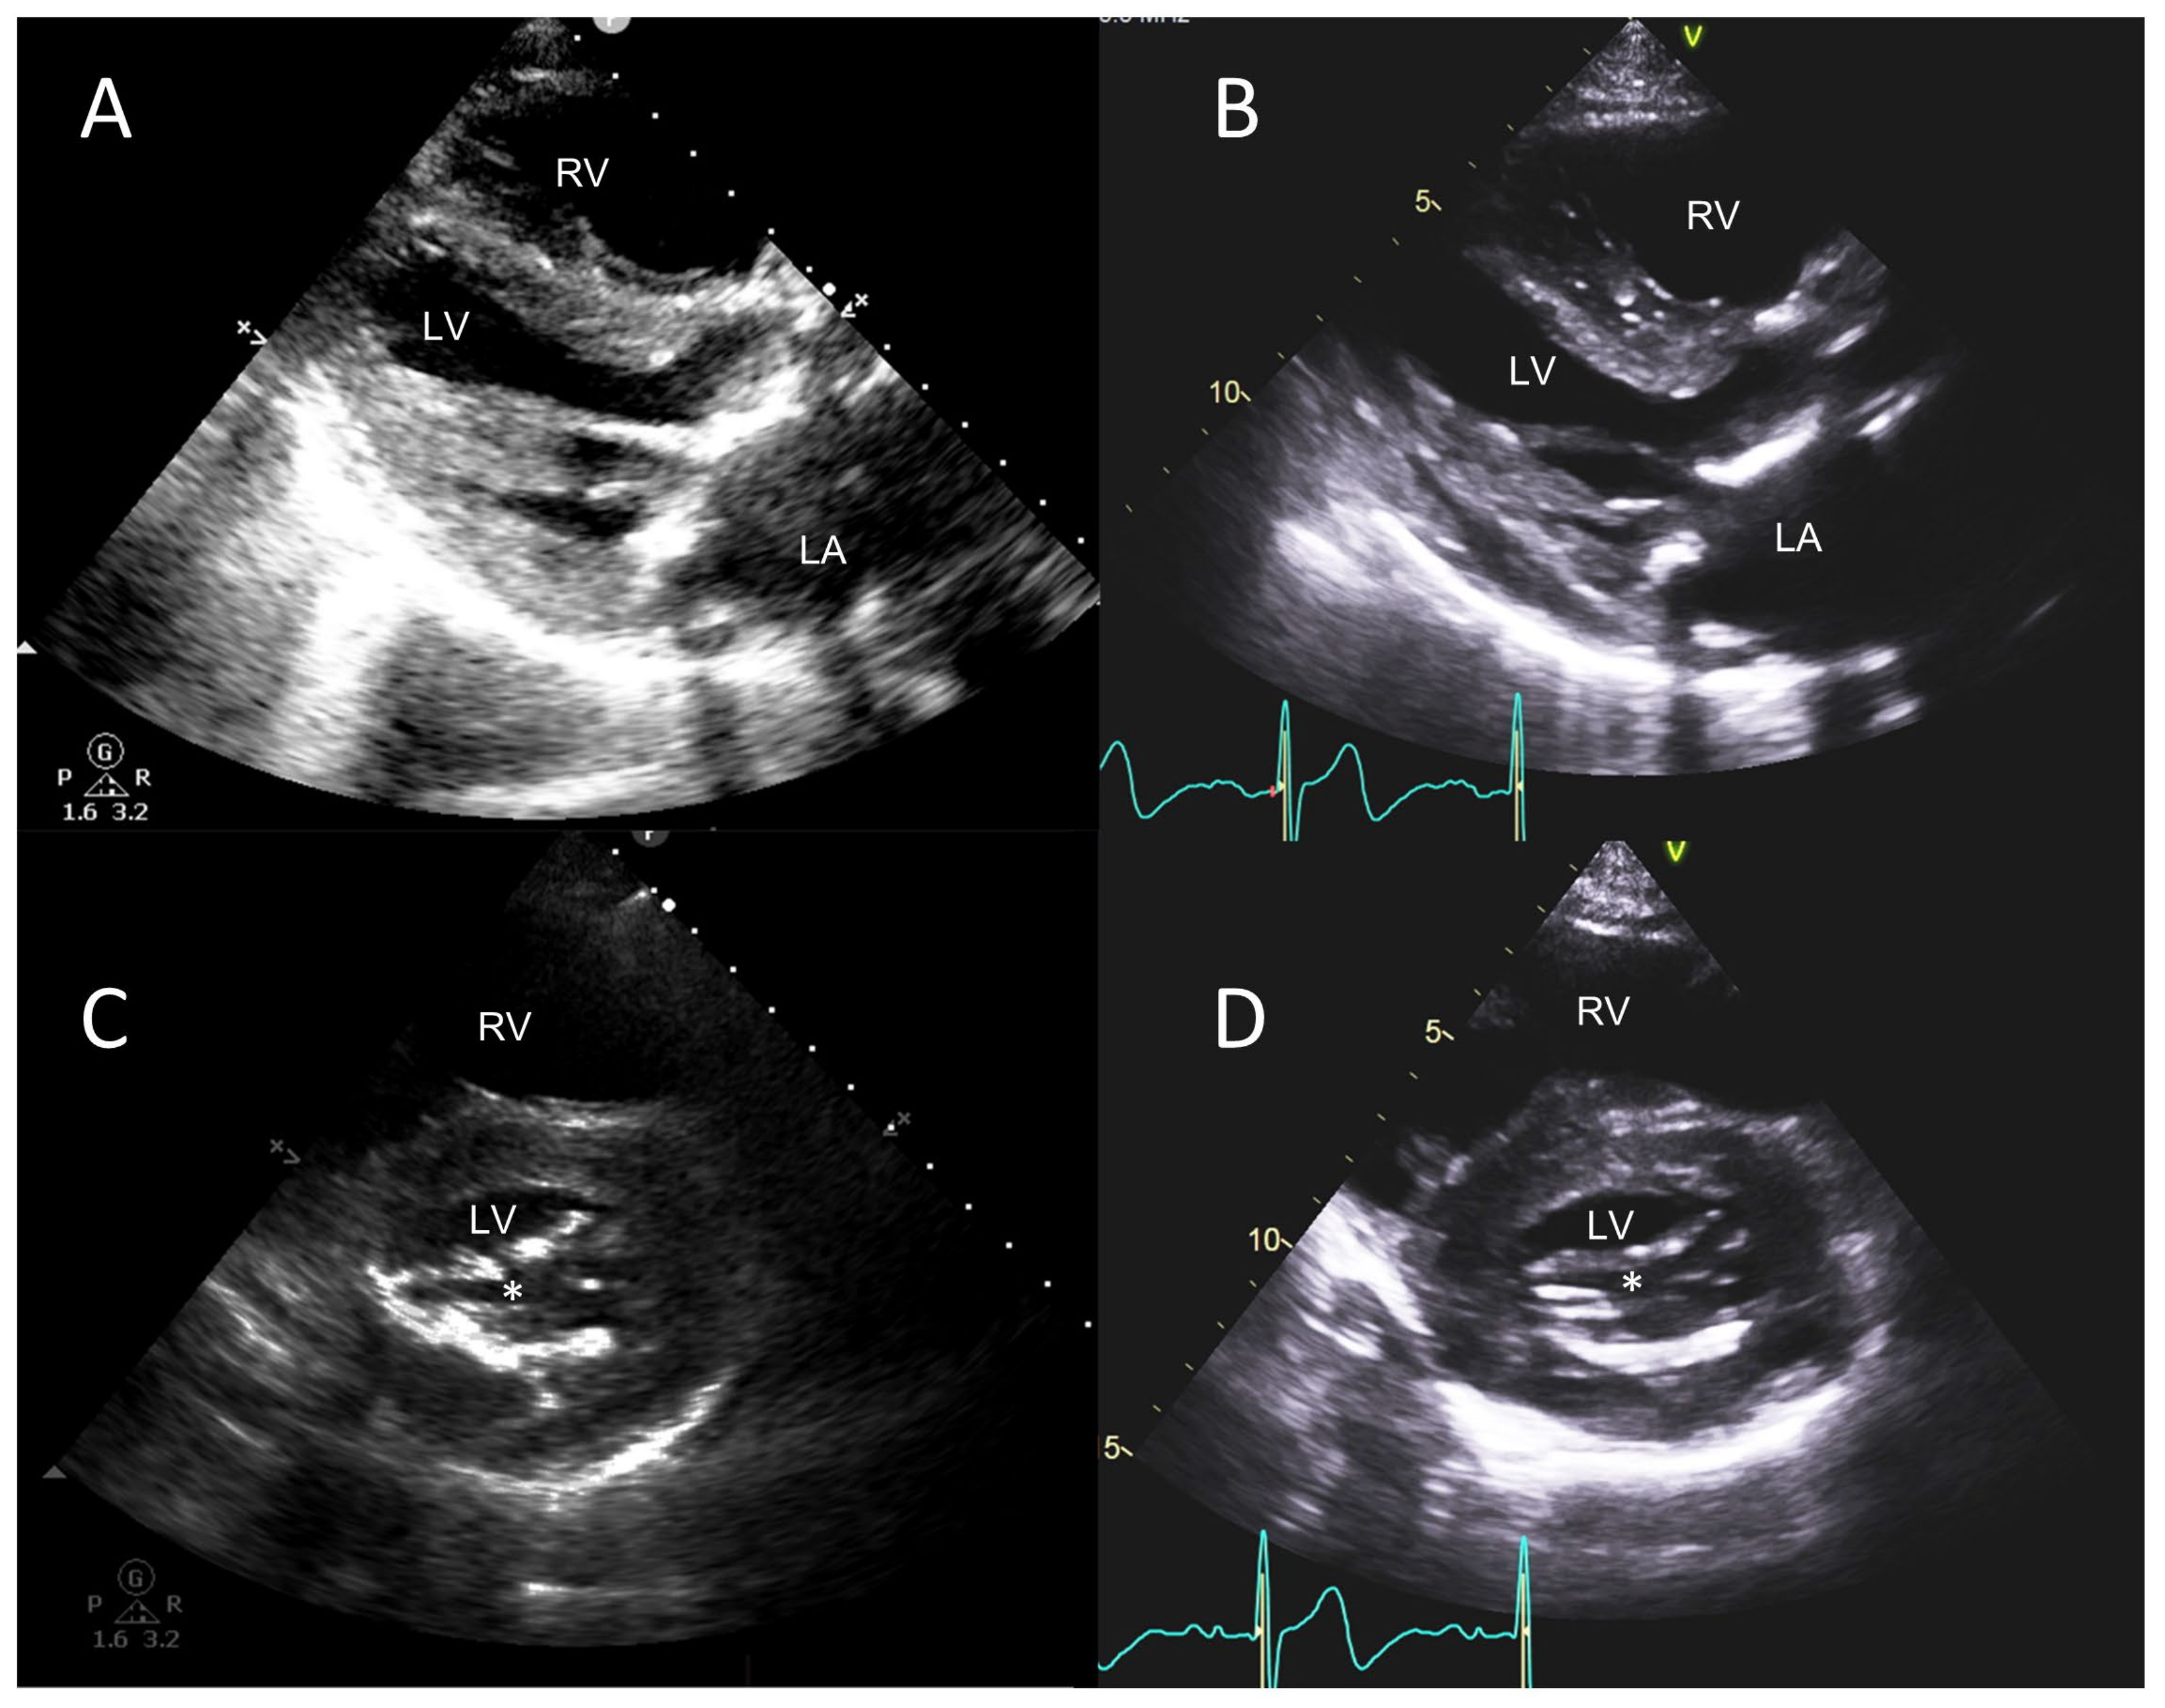

3.2. ≥Moderate Valvular Regurgitation

4.1.2. POCUS with Portable Small Ultrasound Machines